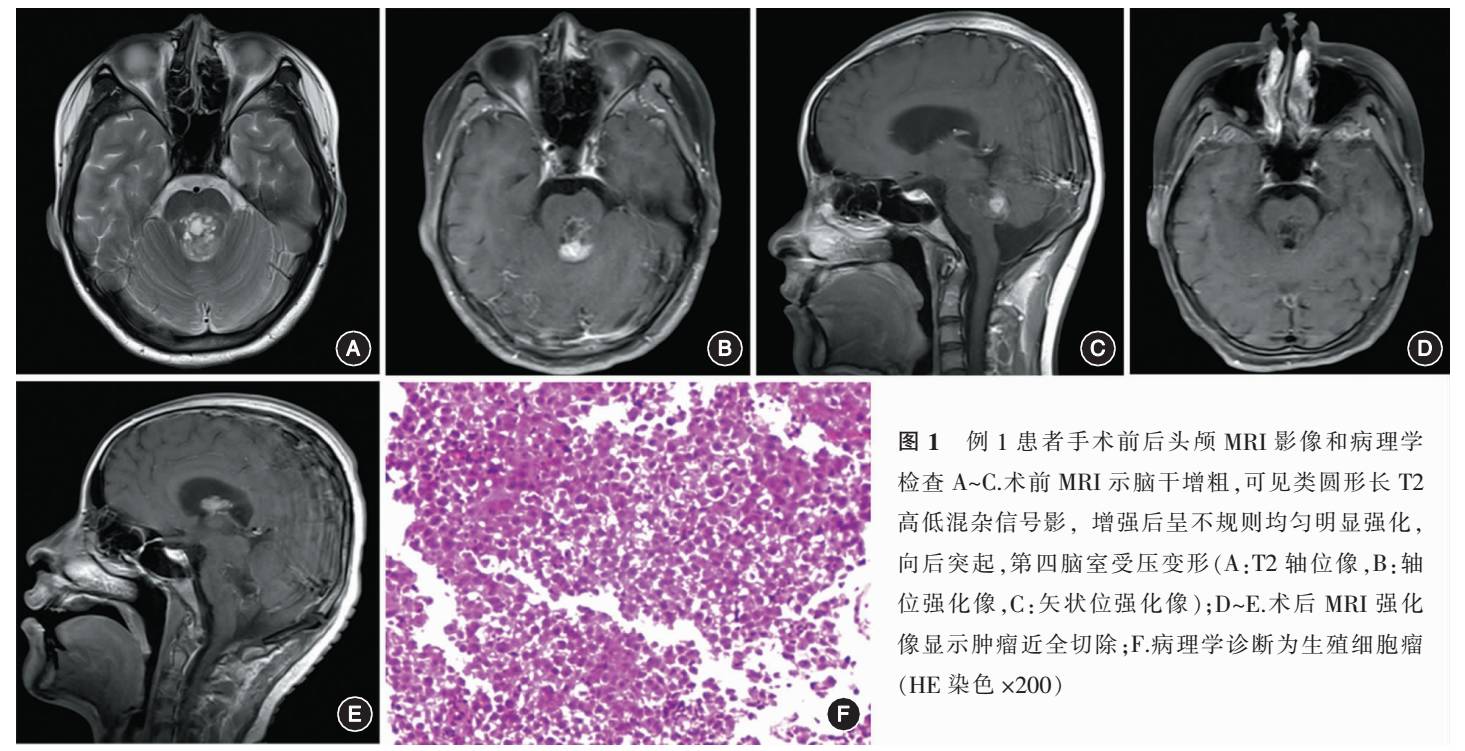

例3 男,17岁。以“视物重影1年”于2012年10月入院。神经系统检查显示,对光反应迟钝,左视时视物重影。头颅MRI显示中脑及双侧丘脑囊实性等、长T1、T2信号影,实质部分均匀明显强化,囊性部分呈不完整环形强化(图3A~D)。术前诊断“生殖细胞瘤、松果体细胞瘤、胶质瘤”可能。行左Poppen入路肿瘤切除术,术中见肿瘤位于中脑顶盖及丘脑、第三脑室内,灰红色,囊实性,囊液为黄绿色,边界不清,与周围脑组织粘连,近全切除病变。病理诊断为生殖细胞瘤,光镜下HE染色肿瘤细胞质淡染,细胞核大而不规则,核仁明显,周围可见新生血管和淋巴细胞(图3E)。免疫组化PLAP、OCT3/4阳性,CD68、AFP阴性,Ki-67 75%。术后行放化疗。随访4年至今,未见复发迹象(图3F),无新增神经系统症状,术前症状恢复。